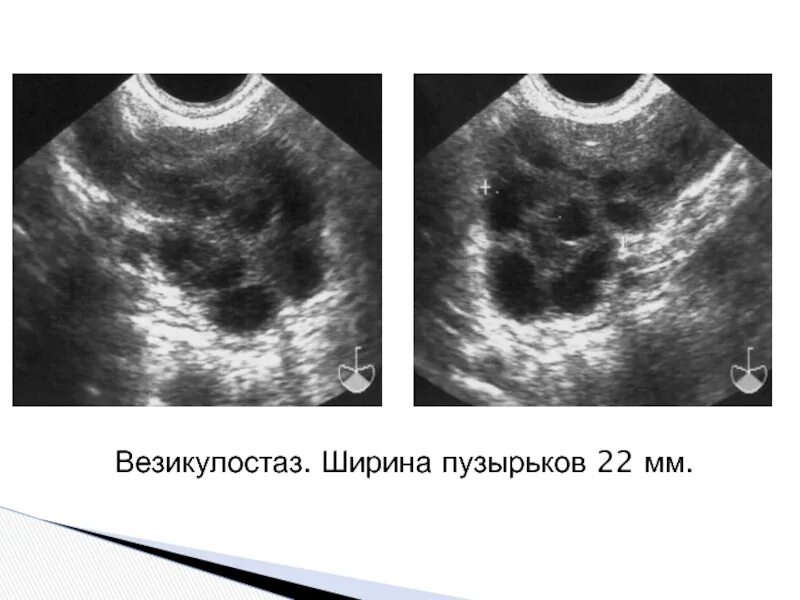

Диффузные предстательной железы